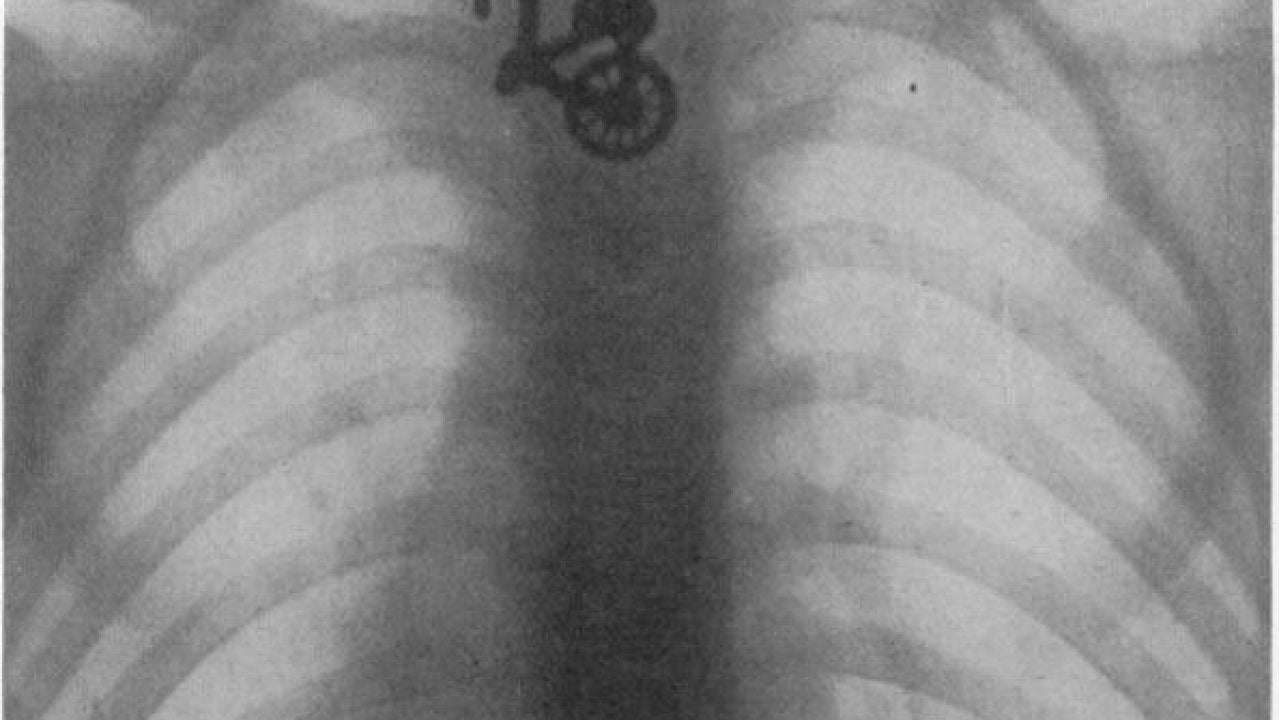

Radiografía del esófago de un niño que se tragó una bicicleta de juguete en 1906. | UCL

Entre lo más inaudito está una radiografía del esófago de un niño que se tragó una bicicleta de juguete en 1906 o el chaval de ocho años, diagnosticado con hiperactividad, que se tragó durante meses los perdigones de los gansos que cazaba y comía su familia como parte de un juego con su hermano.